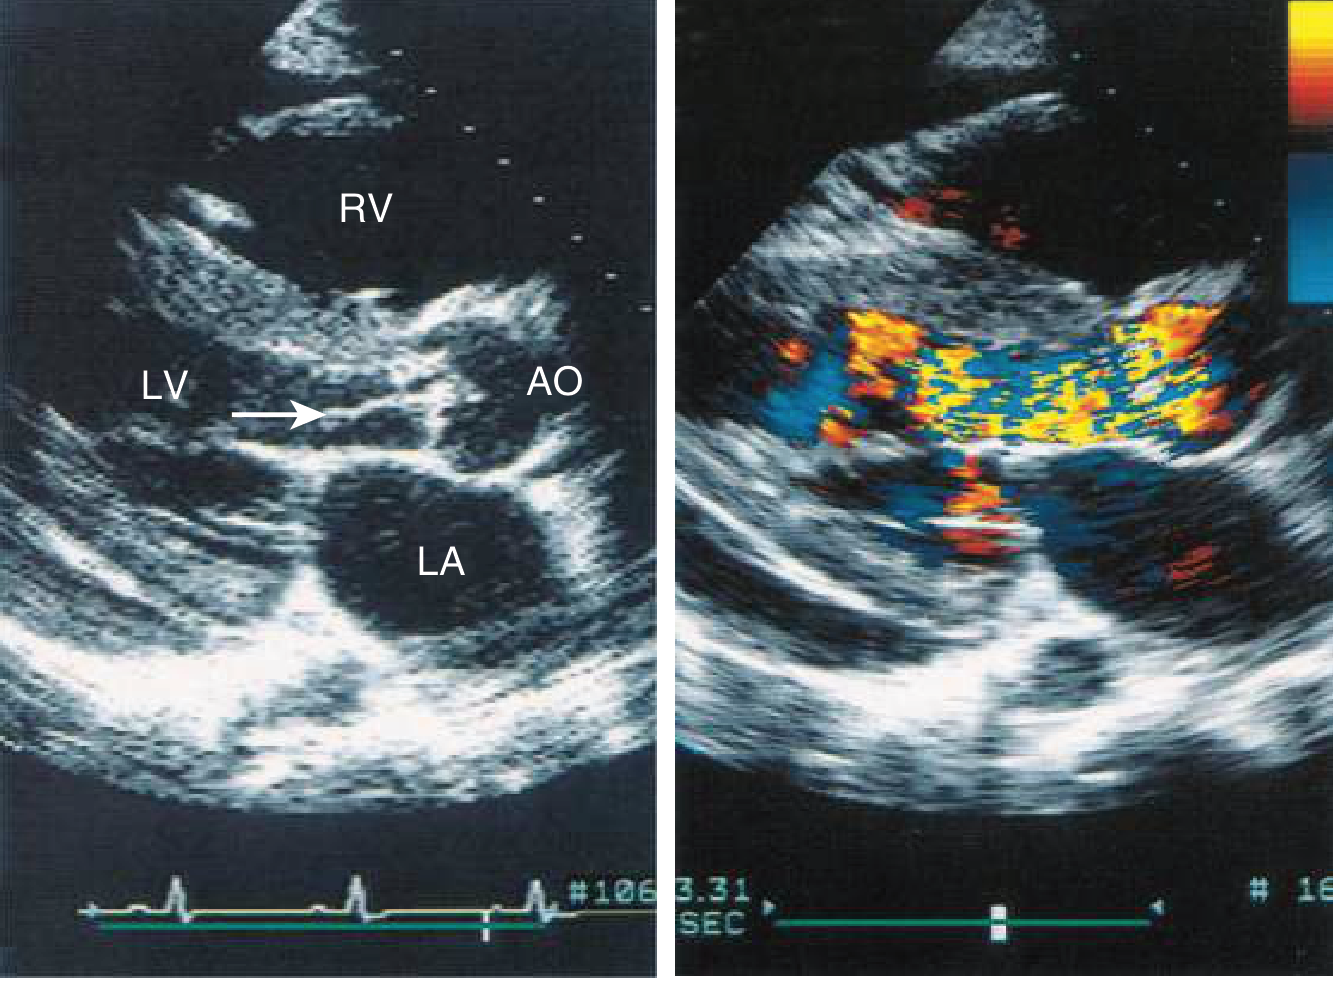

Echocardiogram of aortic regurgitation caused by infective endocarditis showing vegetation and color-flow Doppler

Echocardiogram showing a vegetation prolapsing into the LVOT from the aortic valve leaflet in diastole (left panel), and color-flow Doppler demonstrating turbulent regurgitant flow filling the LV tract during diastole (right panel). — Goldman-Cecil Medicine